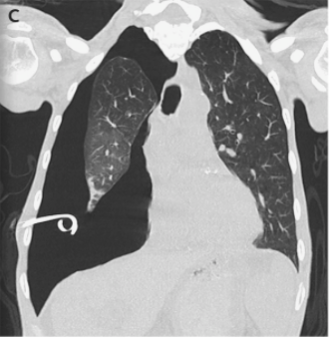

9/ One of the  https://abs.twimg.com/emoji/v2/... draggable="false" alt="🔑" title="Schlüssel" aria-label="Emoji: Schlüssel"> features of lung entrapment is an improvement in dyspnea following a thoracentesis. However, the lung does not fully expand radiographically following the procedure. CT imaging may show a visceral pleura that appears thickened, nodular, or hyperechoic.

https://abs.twimg.com/emoji/v2/... draggable="false" alt="🔑" title="Schlüssel" aria-label="Emoji: Schlüssel"> features of lung entrapment is an improvement in dyspnea following a thoracentesis. However, the lung does not fully expand radiographically following the procedure. CT imaging may show a visceral pleura that appears thickened, nodular, or hyperechoic.

10/ With large pleural effusions, you typically get a contralateral shift of the mediastinum. However, with lung entrapment you will typically see the mediastinum shift ipsilaterally of the effusion or no shift at all. @CritCareMed @PulmCrit @MedEdPGH @gradydoctor